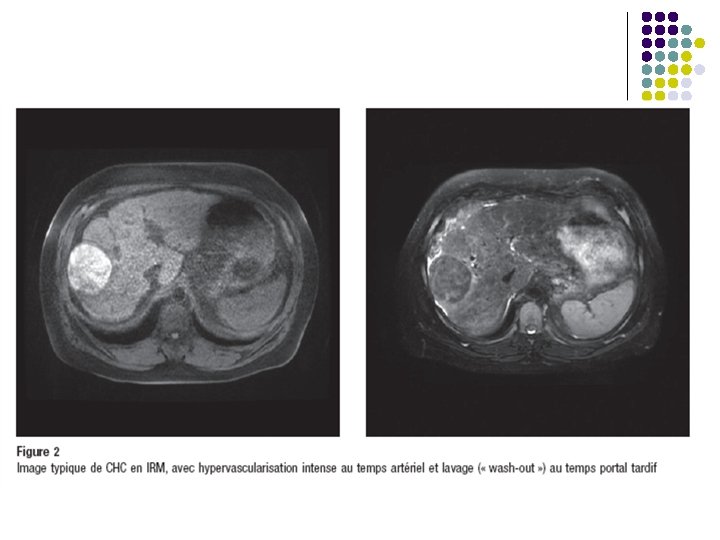

l Diagnostic de CHC l Caractéristiques évocateurs en TDM: Nodule hypervascularisé au temps artériel précoce avec lavage tardif « wash-out » l Critères diagnostiques positifs sur foie cirrhotique l l Histologique compatible ou Nodule < 1 cm: surveillance échographique / 3 mois ou Nodule 1 à 2 cm: 2 images typiques sur TDM et IRM ou Nodule > 2 cm: image hypervascularisée + wash out ou AFP > 200 mcg/l American Association for the Study of liver Diseases. 2005